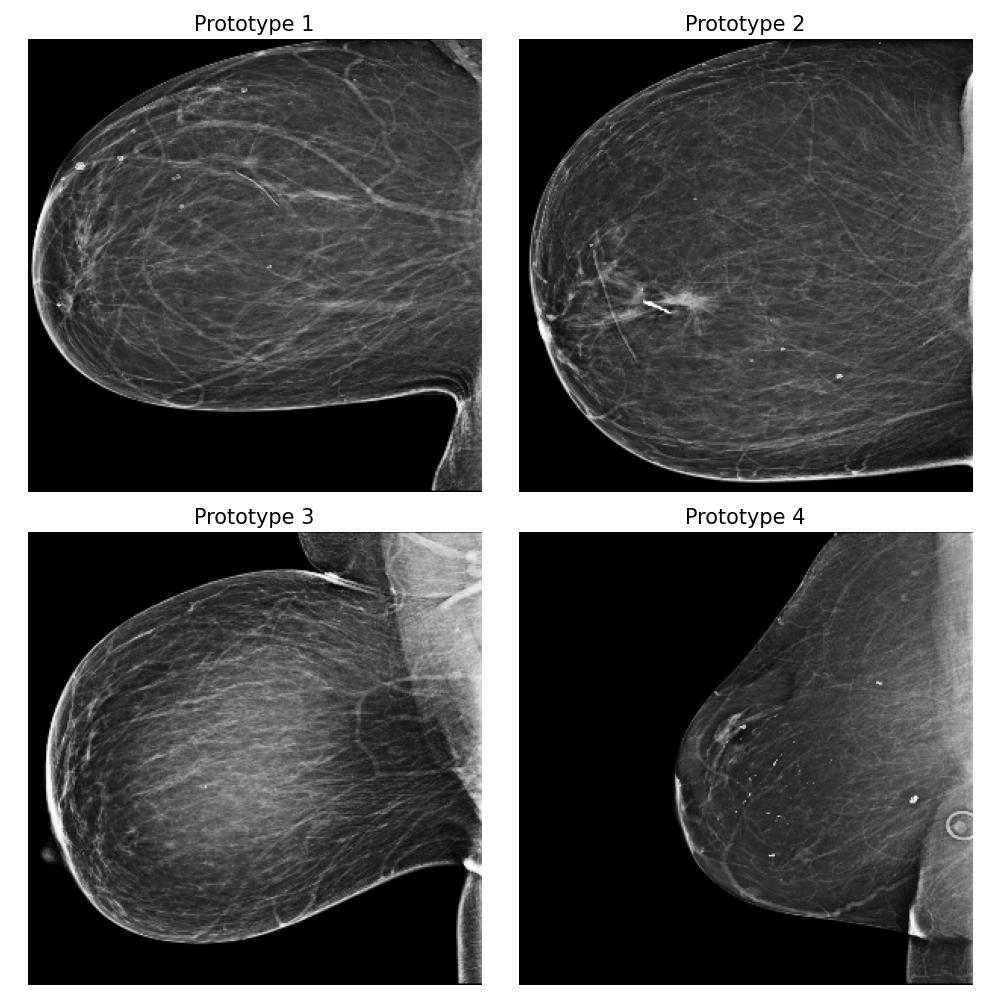

3.5.4 Case Study 2: Medical Image Data - Mammography Patient Population Dataset

In this case study, we assess the effectiveness of our proposed method in a realistic application, focusing on identifying differences between mammograms from two distinct patient populations. Specifically, we simulate a real-world scenario where users deploy models to analyze mammograms of women with varying tissue density distributions — a challenge commonly encountered when comparing premenopausal and postmenopausal patients or younger and older individuals. Premenopausal or younger patients often exhibit denser breast tissue, whereas postmenopausal or older patients often present with less dense tissue (Kim et al., 2020). This dataset evaluation step is crucial before deploying a clinical breast cancer risk detection model across different patient populations.

Dataset and

We use the publicly available EMBED dataset (Jeong et al., 2023). To simulate premenopausal and postmenopausal patient populations, we construct two datasets, and , by randomly sub-sampling from EMBED. Dataset comprises 27,224 mammograms from 8,456 patients with dense breast tissue (density category three in EMBED) and 21,675 mammograms from 7,841 patients in density category two. Dataset includes 27,224 mammograms from 2,715 patients with less dense tissue (density category one) and 21,675 mammograms from 7,797 patients in density category two (medium density). All mammograms were preprocessed to remove clinical markers and aligned such that the breast tissue faces left.

Forming the explanation

For this task, we implemented the “Prototype-summarization-based explanations” described in Section 3.5. We trained a binary vs classifier using the VGG19 feature extractor as backbone and learn four prototypes for each dataset. 97798 mammograms were used for training, and 24450 mammograms were used for testing.

Result

By examining the summarization prototypes shown in Figure 22, we identified tissue density as the primary difference between and . In mammograms, brighter areas correspond to denser tissue. Additionally, we observed that less dense tissue is often associated with larger tissue size. Without our proposed method, human users would need to manually analyze the dataset, which is a labor-intensive and time-consuming task, to reach the same conclusions.

Robustness of the explanation

To examine the robustness of our explanation result, we repeat the explanation algorithm approach on bootstrapped versions of and . Five bootstrapped datasets were constructed by resampling by patients with replacement. As shown in Figure 35 in Appendix Section B.5, we reach the same conclusion for all the bootstrapped datasets.

Coverage evaluation

We again evaluate the coverage quality of the learned set of prototypes using the AUCC score. The coverage curve is shown in Figure 24. We also display the learned latent space for and in Figure 24 and the two datasets and the prototypes are well separated even though they contain overlapping mammograms with density category two (i.e. medium density breasts).